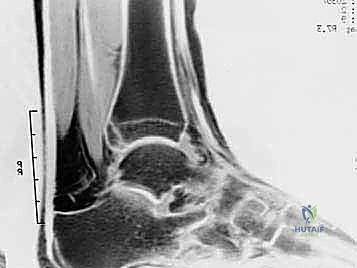

شكل 2: صورة أشعة سينية (X-ray) جانبية للكاحل بوضعية الثني للأسفل، تظهر بوضوح انحشار العظم المثلثي (Os Trigonum) بين الساق والكعب.

| الأشعة السينية (X-ray) | التقييم العظمي الأولي | يظهر العظم المثلثي، بروز ستيدا، الكسور القديمة، النتوءات العظمية. | أساسي ومبدئي. يتم التقاطه بوضعية الثني الأقصى للقدم لإثبات الانحشار الميكانيكي. |